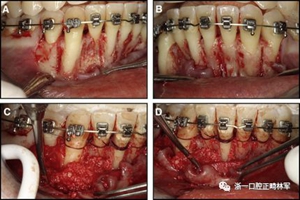

粘合保持器被移除,并放置固定裝置(圖15),僅限于患者要求的下頜弓。在第一階段牙周過程中,將結(jié)締組織移植物置于下頜右側(cè)中切牙的面?zhèn)取?個(gè)月后進(jìn)行第二階段牙周過程(圖16)。包括有意識的垂直骨質(zhì)評分以啟動區(qū)域加速現(xiàn)象,以及顯著的面?zhèn)群蜕鄠?cè)植骨以糾正骨開窗。隨著時(shí)間的推移,全維度弓絲及其表達(dá)的牙齒間扭矩差異顯著改善(圖17)。明智的鄰間減少之后,間隙關(guān)閉擴(kuò)大接觸面,消除不美觀的黑三角。在脫粘之前也校正了牙齒排列和牙弓形態(tài)(圖18)。之前和之后的三維圖像(圖19)突出顯示在下頜右側(cè)尖牙面?zhèn)缺砻嫔瞎堑脑黾右约扒把姥栏恢玫母纳啤S捎谙骂M切牙的伸長被認(rèn)為是不嚴(yán)謹(jǐn)?shù)?,因此輕度前牙開合沒有被矯正。

圖15.下頜右側(cè)中切牙區(qū)域軟組織移植前的初始排齊:A,正面視圖; B,咬合面視圖; C,軟組織移植2周后,初始牙周手術(shù)。

圖16.第二階段牙周手術(shù)階段,軟組織移植后2個(gè)月:A和B,這包括應(yīng)用骨形態(tài)發(fā)生蛋白,故意骨質(zhì)損傷引起局部加速現(xiàn)象,以及C和D,應(yīng)用植骨漿液糾正牙槽骨的開窗(Colin Richman博士提供)。